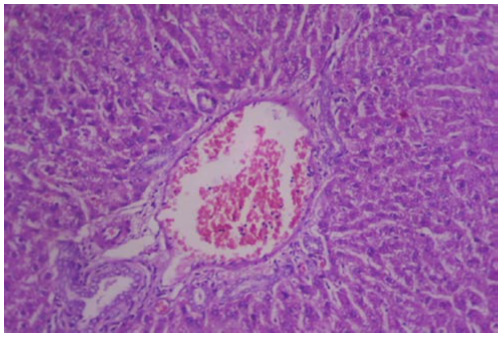

Figure 5.1a is a histological finding of the liver of control adult male Wister Albino Rat using Haematoxylin and Eosin method showing normal Hepatocyte (H), Central Vein (CV), and Sinusoids (S) as indicated using x 400 magnification. While figure 5.1b is a Haematoxylin and Eosin-stained section of kidney of control Wister Albino rat, showing Vascular Glomerular (VG), Bowman’s Capsule (BC), and Renal Tubule (R) as indicated using x 400 magnification.

Figure 5.1a: Group 1 (control) showing a section of the liver of control adult male Wister Albino Rat. H&E 400X.